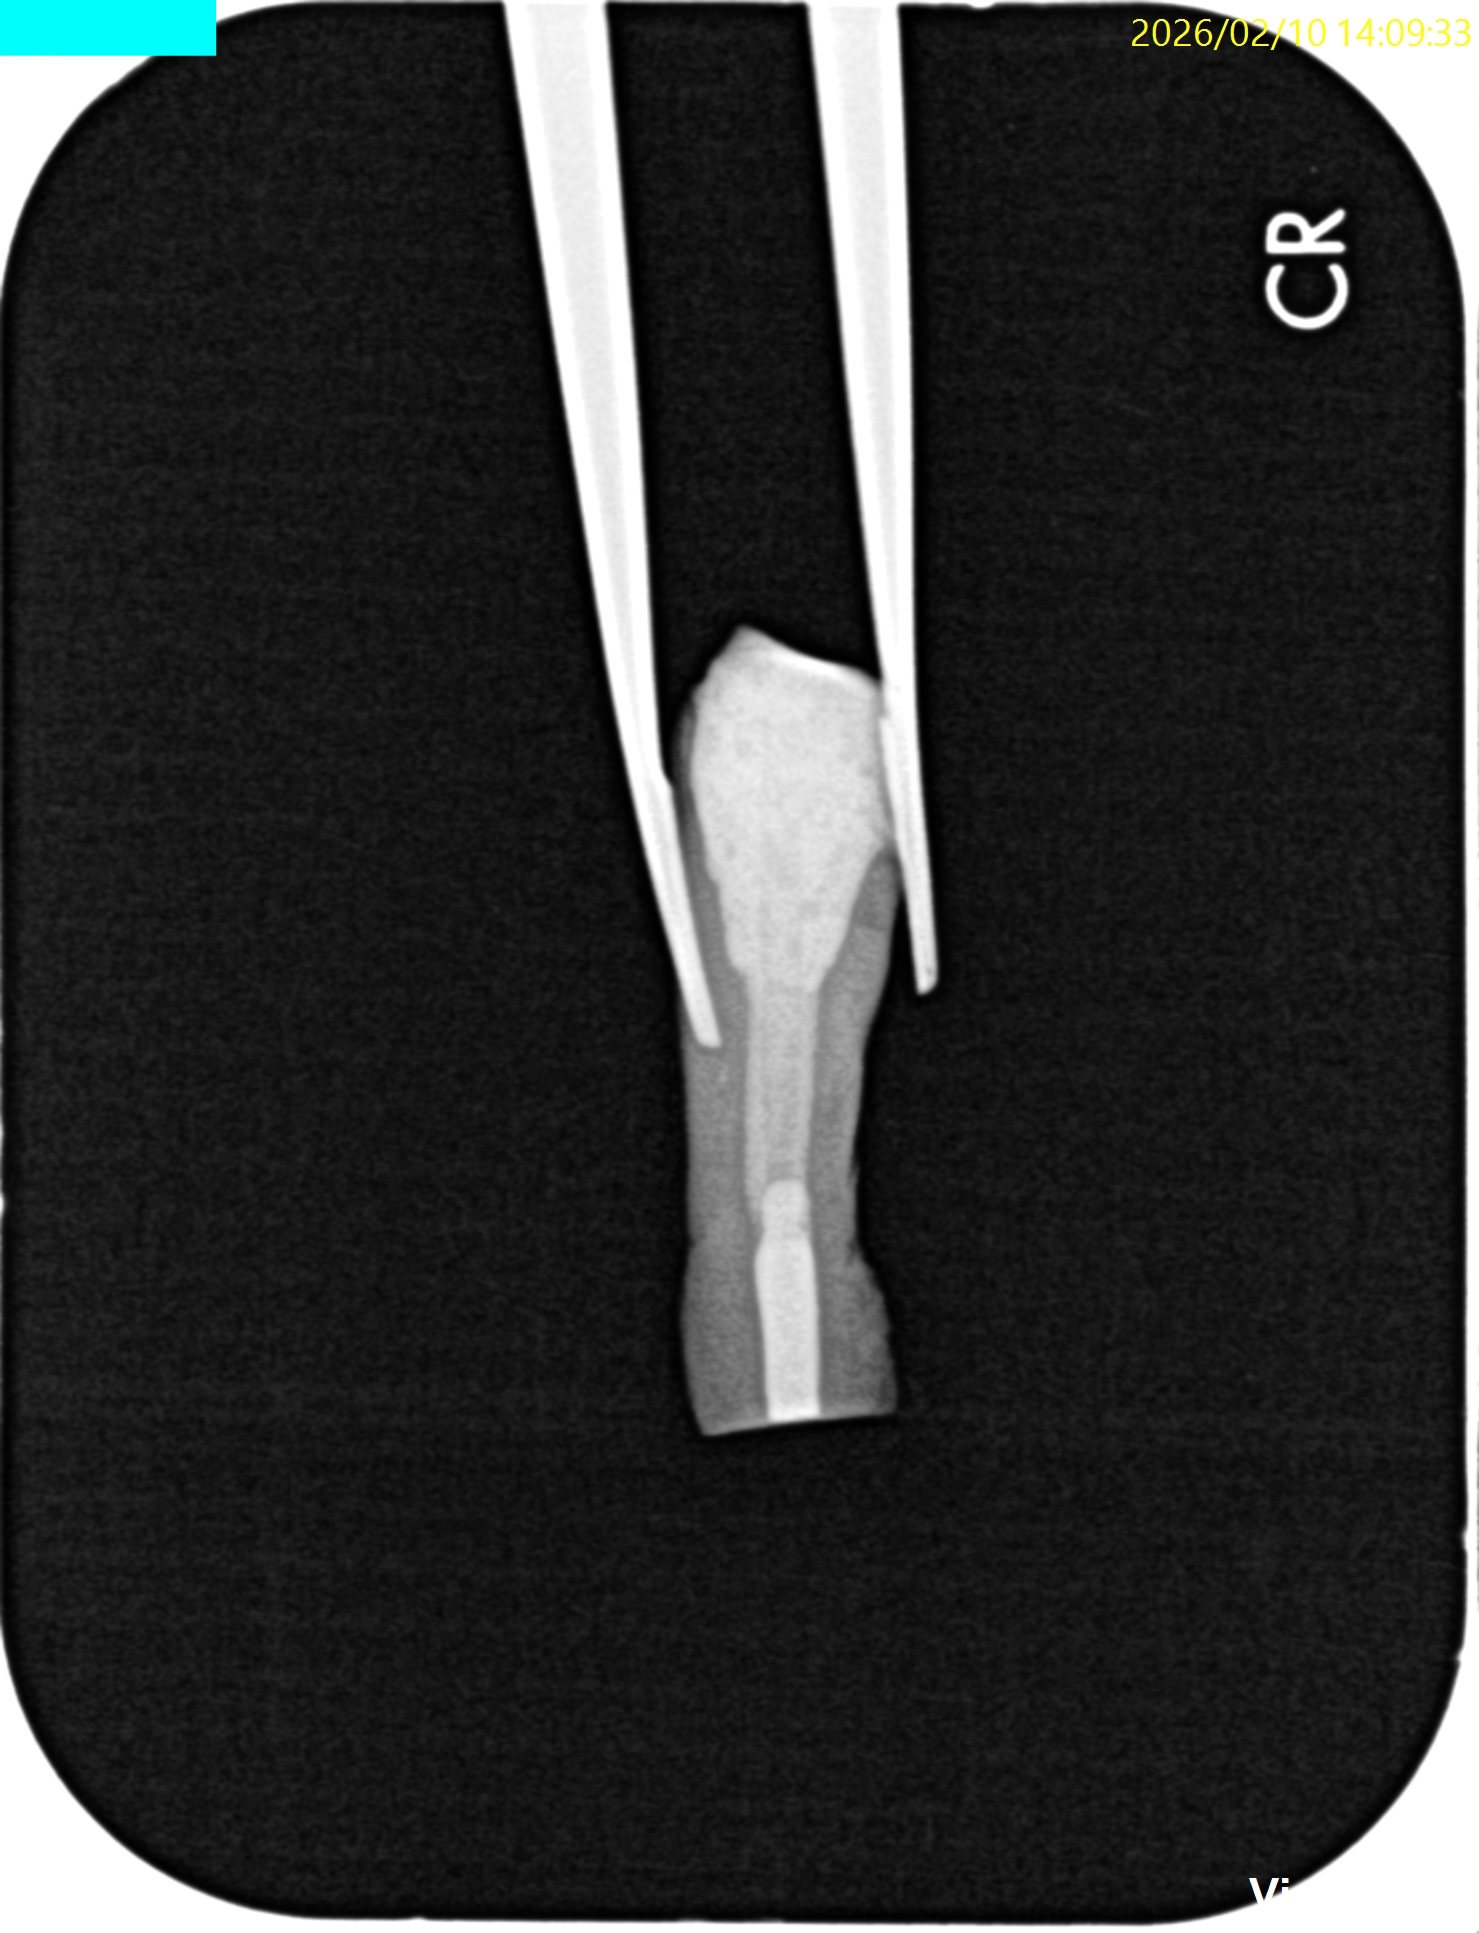

術後にPAを撮影した。

問題はないだろう。